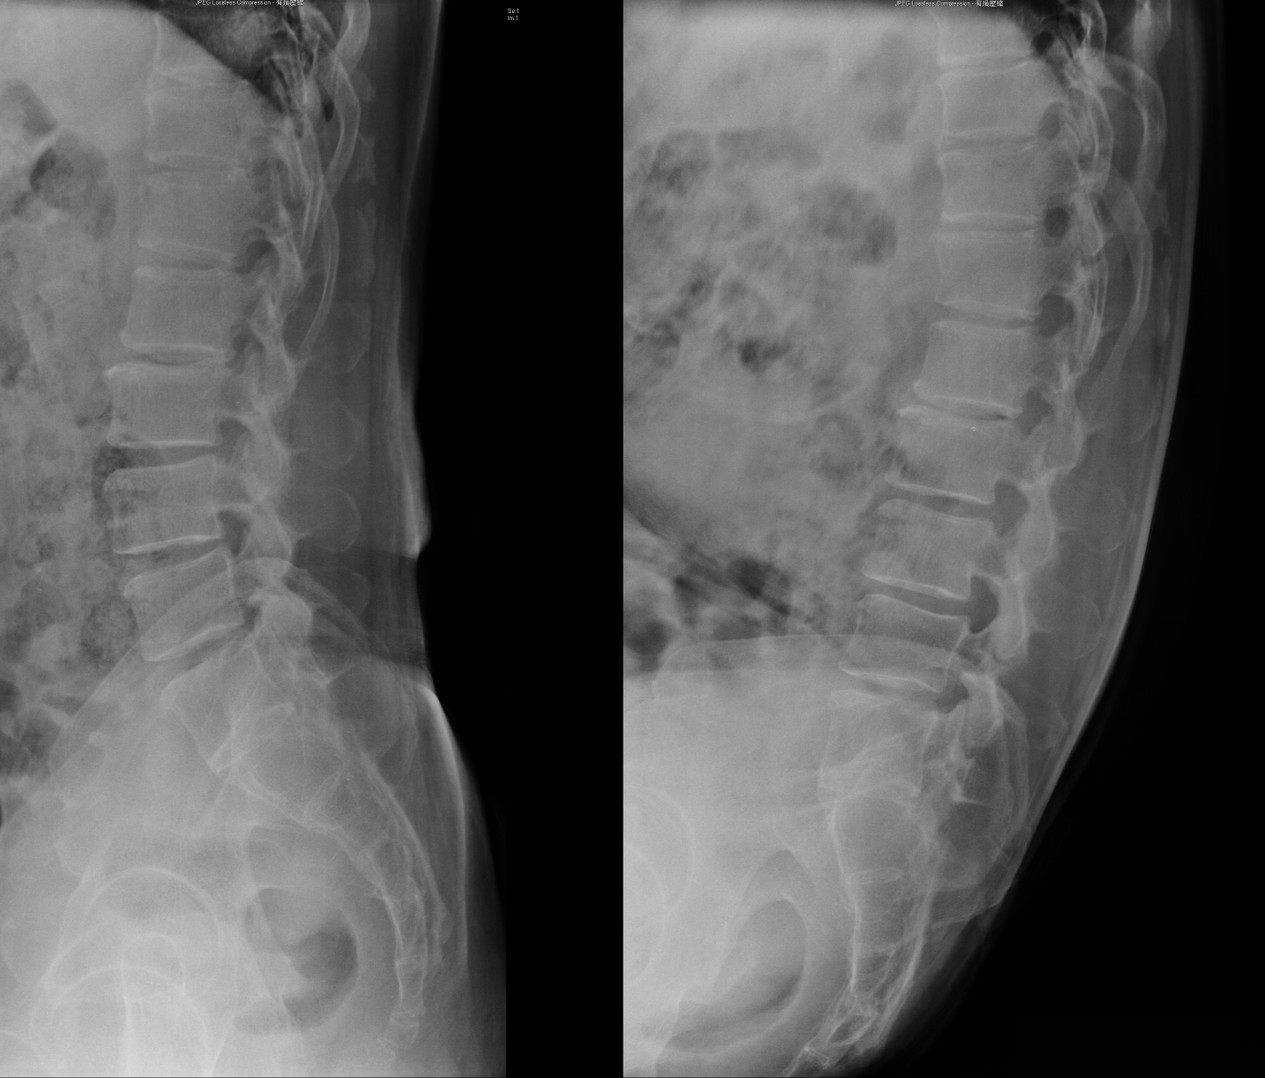

![]() |

| 多節椎間盤退化,第四五腰椎輕度滑脫,無明顯不穩定 |

| 多節椎管狹窄,從第二腰椎至第一薦椎 |